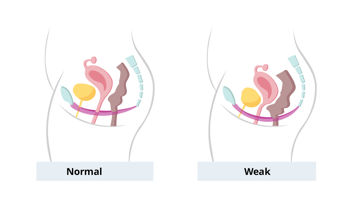

Die Beckenbodendysfunktion (PFD) bezieht sich auf eine breite Konstellation von Symptomen und anatomischen Veränderungen, die mit einer abnormen Funktion der Strukturen innerhalb des Beckenbodenkomplexes zusammenhängen, zu denen das stützende Fasergewebe namens Faszien, die Blut- und Nervenversorgung und insbesondere die Beckenbodenmuskulatur gehören.

Eine Dysfunktion des Beckenbodens ist häufig, wird aber nicht häufig erwähnt. In diesem Artikel finden Sie eine Erklärung über die grundlegende Anatomie des Beckenbodens, eine Beschreibung der Symptome und wie diese behandelt werden können, Informationen,die heruntergeladen und an Ihre Patienten ausgehändigt werden können.

Die Beckenbodendysfunktion (PFD) bezieht sich auf eine breite Konstellation von Symptomen und anatomischen Veränderungen, die mit einer abnormen Funktion der Strukturen innerhalb des Beckenbodenkomplexes zusammenhängen, zu denen das stützende Fasergewebe namens Faszien, die Blut- und Nervenversorgung und insbesondere die Beckenbodenmuskulatur gehören.

Eine Dysfunktion des Beckenbodens ist häufig, wird aber nicht häufig erwähnt. In diesem Artikel finden Sie eine Erklärung über die grundlegende Anatomie des Beckenbodens, eine Beschreibung der Symptome und wie diese behandelt werden können, Informationen,die heruntergeladen und an Ihre Patienten ausgehändigt werden können.